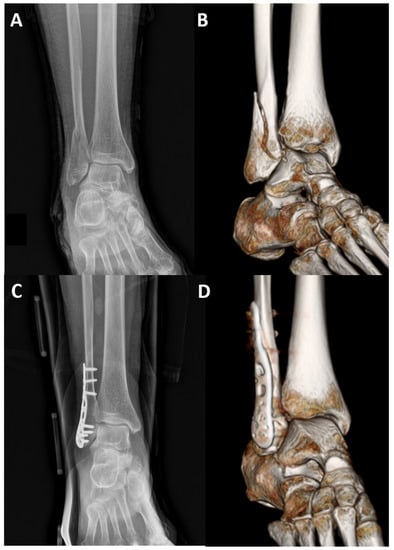

Three-Dimensional Anatomically Pre-Contoured Locking Plate for Isolated Weber B Type Fracture

2.1. Surgical Procedures